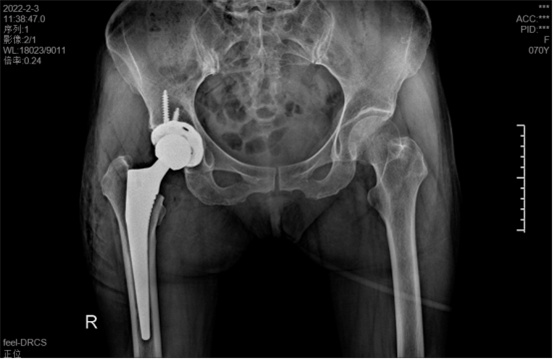

據(jù)羅軍主任介紹,他們首先將鄭阿姨的術(shù)前CT數(shù)據(jù)導(dǎo)入到系統(tǒng)中,通過自動識別骨盆和股骨建立了計算機數(shù)字三維模型。AI HIP顯示患者適合使用合適的髖臼杯、股骨柄、標(biāo)準(zhǔn)陶瓷球頭、陶瓷內(nèi)襯,并精準(zhǔn)定位了截骨線,有效幫助醫(yī)生在手術(shù)中做到精確截骨。

在完善相關(guān)檢查充分評估患者身體情況及手術(shù)風(fēng)險后,羅軍主任改變傳統(tǒng)手術(shù)方式,在易觀俊主治醫(yī)師、柴重喜醫(yī)師等助手的配合下,為鄭阿姨實施了人工智能規(guī)劃輔助DAA入路全髖關(guān)節(jié)置換術(shù)。

術(shù)中假體植入和術(shù)前規(guī)劃完全一致

術(shù)中,醫(yī)生在患者髂前上棘外側(cè)切開約8cm長的切口,小心翼翼地利用闊筋膜張肌與縫匠肌之間的間隙露出髖關(guān)節(jié)。經(jīng)過一番精細、高難度的操作,成功植入人工髖關(guān)節(jié)組件,以取代受損的股骨頭和髖臼。由于手術(shù)切口小,肌肉組織未受損,鄭阿姨恢復(fù)很快,術(shù)后第1天就能下床活動。